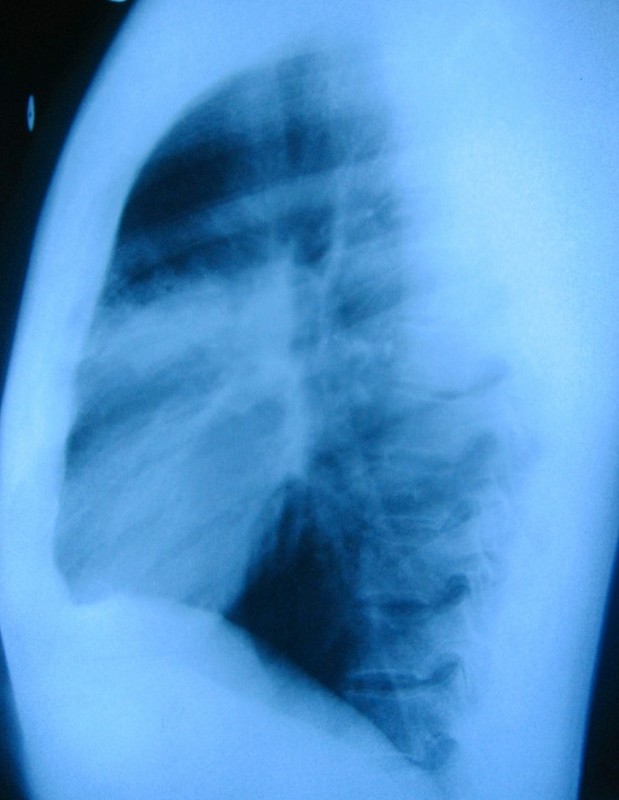

以下是引用谨言慎行在2009-4-24 16:23:00的发言:[br]考虑右肺前段肺炎。治疗14天复查。必要查ct除外占位性病变。

以下是引用随光逐影在2009-4-24 19:40:00的发言:[br]考虑右肺上叶前段肺炎。建议:1)正规抗炎治疗后复查。2)必要时行ct扫描检查排除肿瘤性病变。